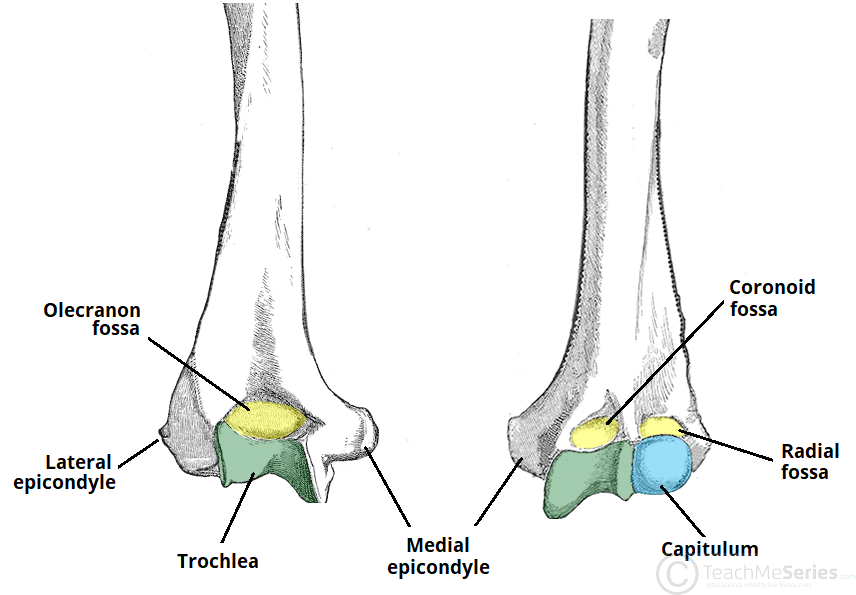

The humerus is a long bone of the upper limb, which extends from the shoulder to the elbow. The proximal aspect of the humerus articulates with the glenoid fossa of the scapula, forming the glenohumeral joint. Distally, at the elbow joint, the humerus articulates with the head of the radius and trochlear notch of the ulna. In this article, we shall look at the anatomy of the humerus – its bony landmarks and clinical correlations. By Anatomography [CC BY-SA 2.1 jp], via Wikimedia Commons Fig 1The anatomical position of the humerus Pro Feature - 3D Model You've Discovered a Pro Feature Access our 3D Model Library Explore, cut, dissect, annotate and manipulate our 3D models to visualise anatomy in a dynamic, interactive way. Learn More Proximal Landmarks The proximal humerus is marked by a head, anatomical neck, surgical neck, greater and lesser tuberosity and intertubercular sulcus. The upper end of the humerus consists of the head. This faces medially, upwards and backwards and is separated from the greater and lesser tuberosities by the anatomical neck. The greater tuberosity is located laterally on the humerus and has anterior and posterior surfaces. It serves as an attachment site for three of the rotator cuff muscles – supraspinatus, infraspinatus and teres minor – they attach to superior, middle and inferior facets (respectively) on the greater tuberosity. The lesser tuberosity is much smaller, and more medially located on the bone. It only has an anterior surface. It provides attachment for the last rotator cuff muscle – the subscapularis. Separating the two tuberosities is a deep groove, known as the intertubercular sulcus. The tendon of the long head of the biceps brachii emerges from the shoulder joint and runs through this groove. The edges of the intertubercular sulcus are known as lips. Pectoralis major, teres major and latissimus dorsi insert on the lips of the intertubercular sulcus. This can be remembered with the mnemonic “a lady between two majors”, with latissimus dorsi attaching between teres major on the medial lip and pectoralis major laterally. The surgical neck extends from just distal to the tuberosities to the shaft of the humerus. The axillary nerve and circumflex humeral vessels lie against the bone here. By TeachMeSeries Ltd (2025) Fig 2The proximal aspect of the humerus. Note the greater and lesser tuberosities as a site of attachment for muscles. Clinical Relevance Surgical Neck Fracture The surgical neck of the humerus is a frequent site of fracture – usually by a direct blow to the area, or falling on an outstretched hand. The key neurovascular structures at risk here are the axillary nerve and posterior circumflex artery. Axillary nerve damage will result in paralysis to the deltoid and teres minor muscles. The patient will have difficulty performing abduction of the affected limb. The nerve also innervates the skin over the lower deltoid (regimental badge area), and therefore sensation in this region may be impaired. Shaft The shaft of the humerus is the site of attachment for various muscles. Cross section views reveal it to be circular proximally and flattened distally. On the lateral side of the humeral shaft is a roughened surface where the deltoid muscle attaches. This is known is as the deltoid tuberosity. The radial (or spiral) groove is a shallow depression that runs diagonally down the posterior surface of the humerus, parallel to the deltoid tuberosity. The radial nerve and profunda brachii artery lie in this groove. The following muscles attach to the humerus along its shaft: Anteriorly – coracobrachialis, deltoid, brachialis, brachioradialis. Posteriorly – medial and lateral heads of the triceps (the spiral groove demarcates their respective origins). Clinical Relevance Mid-Shaft Fracture A mid-shaft fracture of the humerus risk damage to the radial nerve and profunda brachii artery (as they are tightly bound in the radial groove). The radial nerve innervates the extensors of the wrist. In the event of damage to this nerve (either direct or as a consequence of swelling), the extensors will be paralysed. This results in unopposed flexion of the wrist, known as ‘wrist drop’. There can also be some sensory loss over the dorsal (posterior) surface of the hand, and the proximal ends of the lateral 3 and a half fingers dorsally. By Shoulderdoc.co.uk [CC BY-SA 2.0] Fig 3Wristdrop of the left forearm, as a result of radial nerve palsy. Distal Region The lateral and medial borders of the distal humerus form medial and lateral supraepicondylar ridges. The lateral supraepicondylar ridge is more roughened, providing the site of common origin of the forearm extensor muscles. Immediately distal to the supraepicondylar ridges are extracapsular projections of bone, the lateral and medial epicondyles. Both can be palpated at the elbow. The medial is the larger of the two and extends more distally. The ulnar nerve passes in a groove on the posterior aspect of the medial epicondyle where it is palpable. Distally, the trochlea is located medially, and extends onto the posterior aspect of the bone. Lateral to the trochlea is the capitulum, which articulates with the radius. Also located on the distal portion of the humerus are three depressions, known as the coronoid, radial and olecranon fossae. They accommodate the forearm bones during flexion or extension at the elbow. By TeachMeSeries Ltd (2025) Fig 4Bony landmarks of the distal humerus. It articulates with the radius and ulna to form the elbow joint. Articulations The proximal region of the humerus articulates with the glenoid fossa of the scapula to form the glenohumeral joint (shoulder joint). Distally, at the elbow joint, the capitulum of the humerus articulates with the head of the radius and the trochlea of the humerus articulates with the trochlear notch of the ulna. Clinical Relevance Supracondylar Fracture A supracondylar fracture is a fracture of the distal humerus just above the elbow joint. The fracture is typically transverse or oblique, and the most common mechanism of injury is falling on an outstretched hand. It is more common in children than adults. In this type of injury, the brachial artery can be damaged; either directly, or via swelling following the trauma. The resulting ischaemia can cause Volkmann’s ischaemic contracture – uncontrolled flexion of the hand – as flexor muscles become fibrotic and short. There also can be damage to the anterior interosseous nerve (branch of the median nerve), ulnar nerve or radial nerve. The anterior interosseous nerve can be tested by asking the patient to make an ‘okay’ sign, testing for weakness of flexor pollicis longus. The Gartland classification is used for these fractures: Type 1 is minimally displaced Type 2 is displaced with but with an intact posterior cortex Type 3 is completely off-ended. Type 1 can usually be managed conservatively with an above elbow cast whereas types 2 and 3 typically require surgical fixation with crossed, bi-cortical k-wires. By TeachMeSeries Ltd (2025) Fig 5A supracondylar fracture of the humerus Do you think you’re ready? Take the quiz below Pro Feature - Quiz The Humerus Question 1 of 3 Submitting... Skip Next Rate question: You scored 0% Skipped: 0/3 1800 More Questions Available Upgrade to TeachMeAnatomy Pro Challenge yourself with over 1800 multiple-choice questions to reinforce learning Learn More Rate This Article